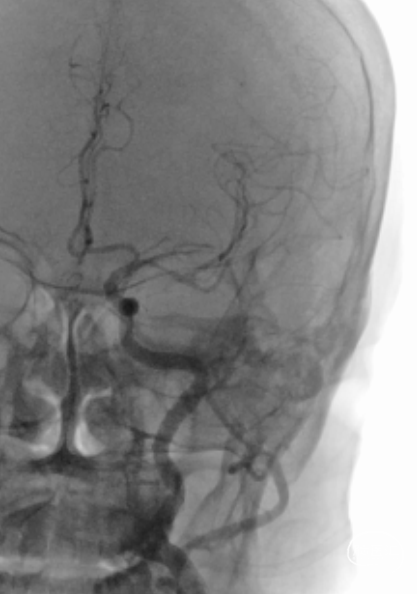

术前造影提示:左侧大脑中动脉闭塞,可见部分豆纹动脉显影,左侧大脑前动脉通过脑膜支代偿左侧大脑中上干。

中年男性患者,起病急,病情有进展加重表现,造影提示左侧大脑中动脉近端以远闭塞,大脑前部分代偿,造影闭塞为椎形征,考虑脑梗死发病机制为ICAS可能性大。拟行“BASIS技术”取栓及开通左侧大脑中动脉闭塞必要行支架植入术治疗。